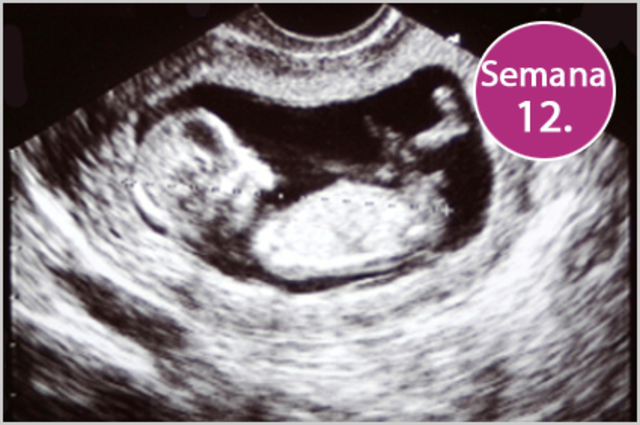

• 12 SEMANA

12 SEMANA

el feto mide 9cm. y pesa entre 15 y 20 gramos. La cabeza disminuye su ritmo de crecimiento, para estar más proporcionada respecto al cuerpo. Los brazos y piernas se alargan, separándose los dedos de manos y pies. Comienzan a esbozarse las uñas. Aparece en el feto el reflejo de succión, que será tan importante para su alimentación en la vida extrauterina.